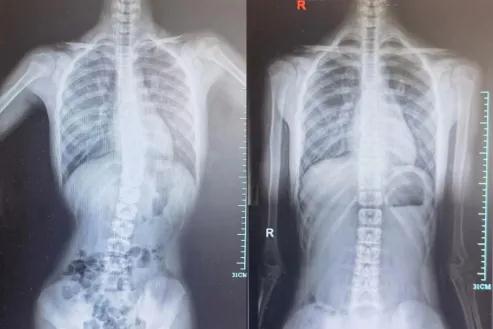

在进行详细的体格检查后,詹院长发现小明高低肩明显,背部肌肉局部紧张,经全脊柱的X线检查后,结果显示小明的Cobb角约15°,就像被拧过的麻花,属于典型的脊柱侧弯。